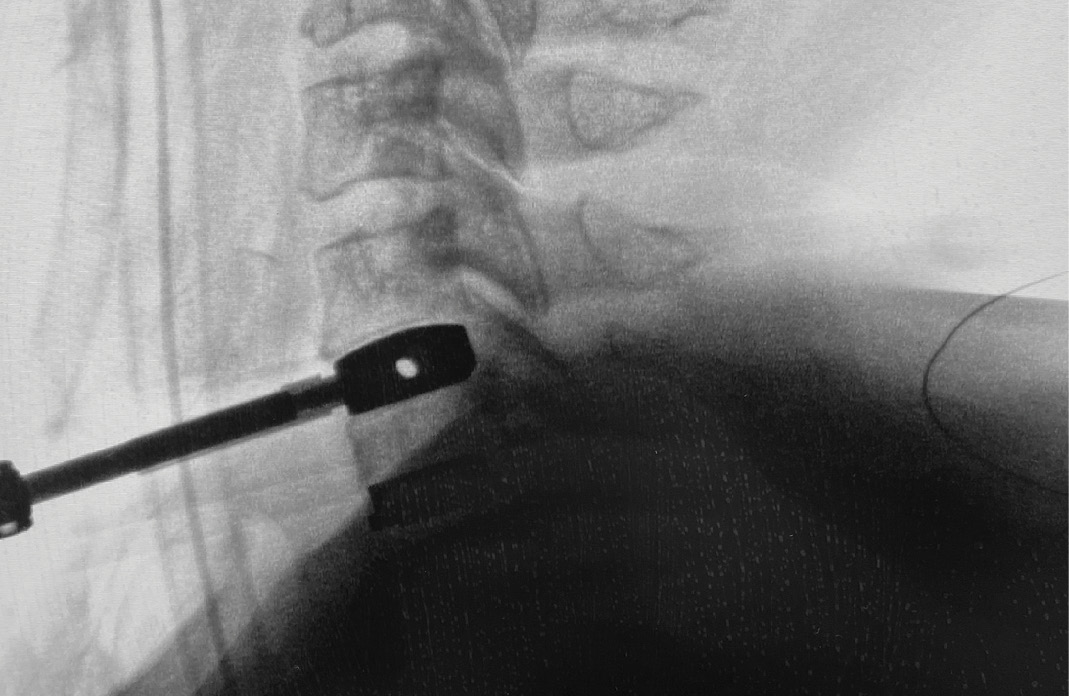

During intra-operative trialing after discectomy and foraminotomies, I felt that the best fit at the C6-7 level was with a prodisc C SK—6mm tall by 18mm deep (Figure 6a). I then performed the discectomy and trialing at the C5-6 level and felt that the prodisc C Vivo was a perfect fit here (Figure 6b).

The patient’s symptoms have completely resolved. The x-rays in Figure 8 were taken at the first post-op visit at 2 weeks.